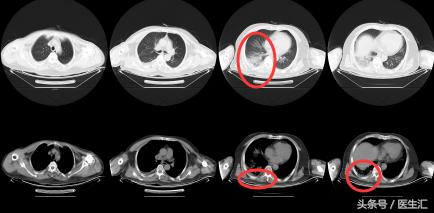

【 胸部 CT】2016.10.05

结果示:

本病例表现很普通,在临床上经常会碰到这种类型的,拿到这个病例首先可能会考虑是肺炎,但是真的是肺炎吗?为了明确诊断,再次详细问了患者的病史,下面来看看患者的病史特点,然后进行分析: